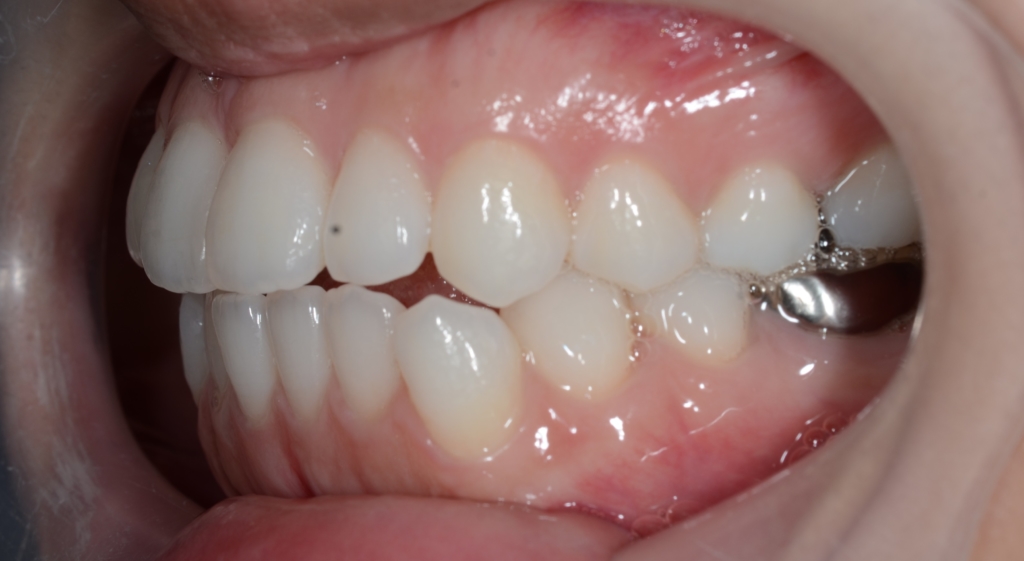

いわゆる顎は出来たのですが、緑の線で囲まれた口元の部分が出ていて、スッキリしない状況です。

また、お口を閉じるのに「力」が必要で、オトガイ部にその緊張に伴うシワが見られます。

Eラインという一点に絞れば希望はそれなりに叶ったのですが、横顔と口元という全体的なバランスで捉えると、「何か口元が出ている!」という状態でした。